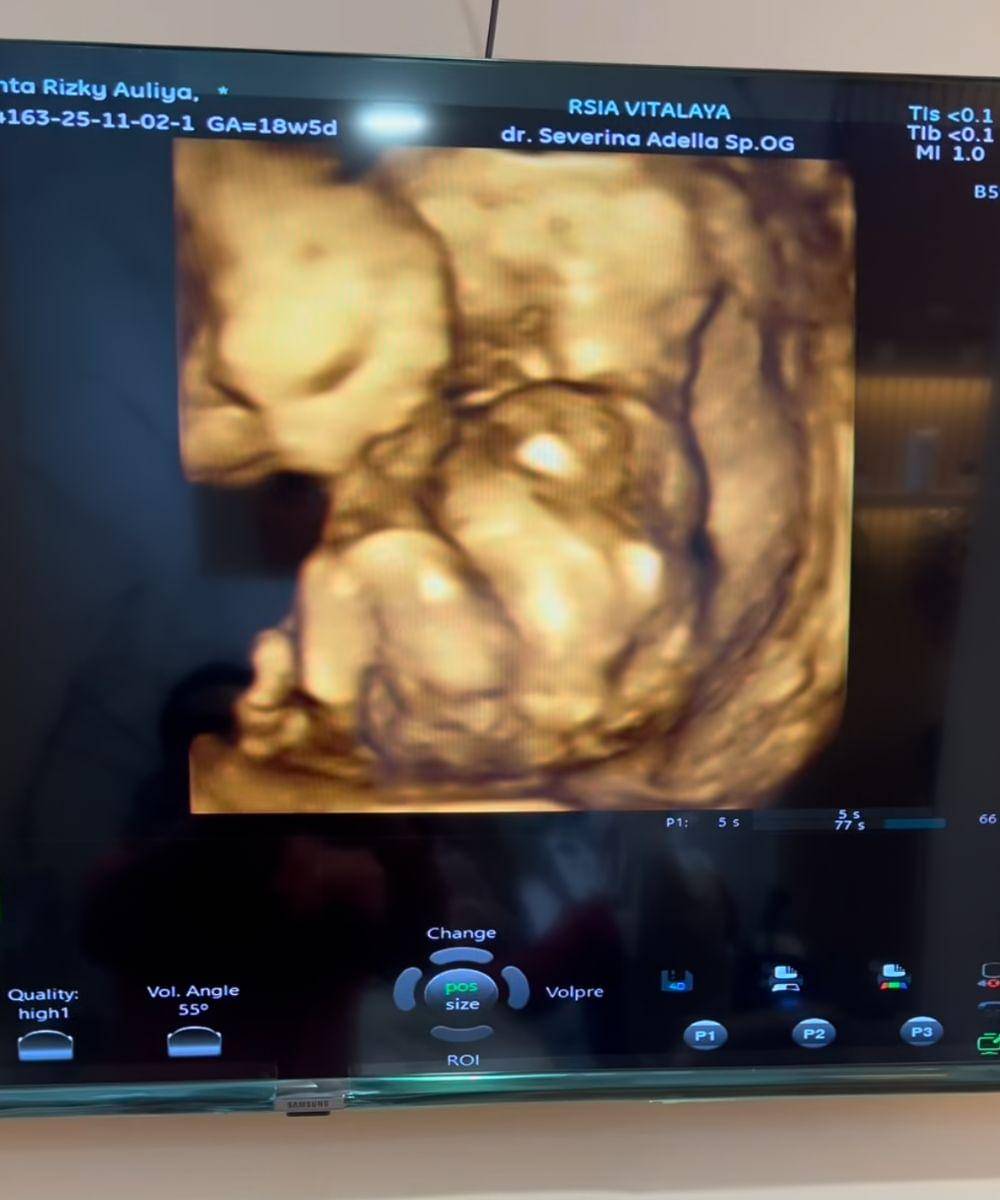

4. Periksa kehamilan untuk mempersiapkan gender reveal

Baru-baru ini, Chaca membagikan video yang memperlihatkan momen hangat saat melakukan pemeriksaan kehamilan bersama sang suami, Ricky Perdana, dan mama mertua. Dalam video tersebut, Chaca tampak melakukan USG untuk memantau kondisi janin sekaligus mengetahui jenis kelamin calon anak ketiganya.

Momen ini menunjukkan betapa antusiasnya Chaca dan keluarga dalam menyambut kehadiran si Kecil. Tampak sang suami dan mama mertua yang bahagia melihat perkembangan bayi di layar monitor.

Namun, rasa penasaran penggemar belum terjawab sepenuhnya. Di akhir video, Chaca memberi isyarat bahwa hasil USG terkait jenis kelamin sang bayi belum akan diungkap, karena akan dilanjutkan di part 2 kontennya. Ini tentu membuat para pengikutnya semakin menantikan kelanjutan kisah manis perjalanan kehamilan ketiga Chaca.